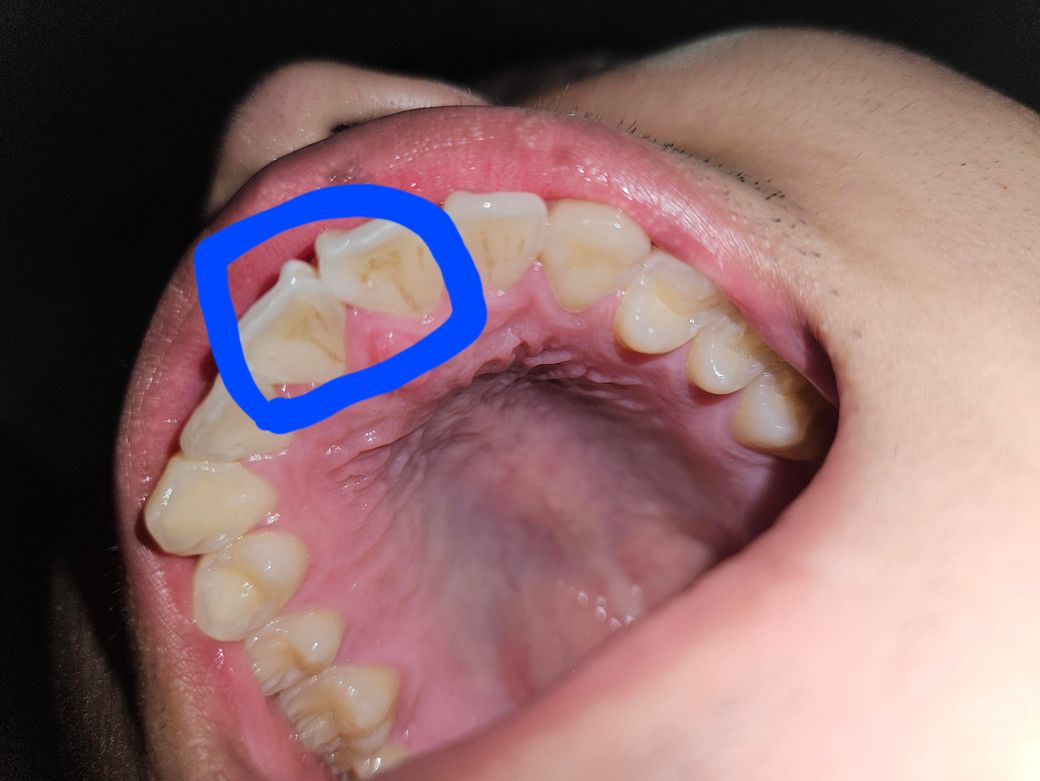

오늘 부정교합 때문에 윗니를 살짝 갈았는데 이게 맞는걸까여?

제가 윗니랑 아랫니가 너무 맞닿아서 병원에서 윗 이빨을 갈아주셨는데. 약간 어색하고 불편함도 있는거 같아서 이게 맞는건지 궁금합니다.. 너무 어색하네여

• 1번 째 사진

사진상에는 특별히 문제가 되는 것은 모르겠습니다. 교합이 여전히 안맞다면 다시 말씀드려야 합니다.